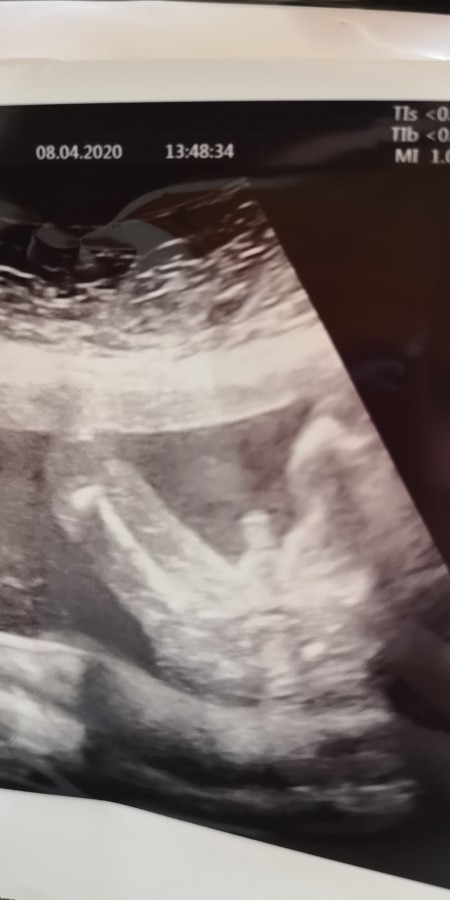

Sizce bu göbek kordonumu

Sizce bu göbek kordonu mu

Gebelik haftası

17

Canm bu pipisi yakınlaştırdıhı için büyük çıkmış hatta pipi de değil torbası varya scrotum torbası o erkek bu benm de oğlum olacak onunda böyle öğrendk

Bana biraz büyük gibi geldi. Benim oğlumunk ultrasondai baya minik duruyordu çünkü. Sağlıklıca doğsunda gerisi önemli ddğiş